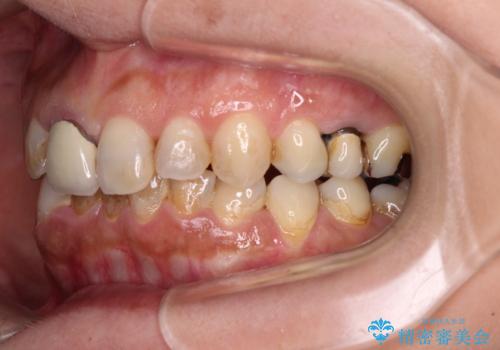

- 上下前歯のデコボコと、治療途中の歯を気にして来院された患者様です。

ご家族がインビザラインにて矯正治療を行っていたため、ご本人の希望によりインビザラインによるマウスピース矯正を行うこととしました。

根管治療が必要な歯は事前に処置を行った上で矯正治療を開始し、概ね歯列が整ったところでセラミッククラウンなどに置き換え、その後インビザラインを1セット使用して仕上げていくこととしました。